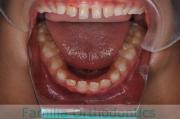

No.22V-759

- 叢生

- 上顎前突

- 32歳

- 女性

- 上:

- non

- 下:

- 主な使用装置:

- Invisalign

- 治療にかかった費用:

- 95万円

上の前歯の並びが気になるのできれいにしたい、ということで来院されました。マウスピース型矯正装置のひとつ、インビザライン/InvisalignR(薬機法および医薬品副作用被害救済制度の対象外)を用いて治療しました。

非抜歯で2年弱、20回程度の通院で治療が完了しました。

マウスピース矯正は、患者さんの協力に治療結果が左右されるところはリスクと言えるかもしれません。